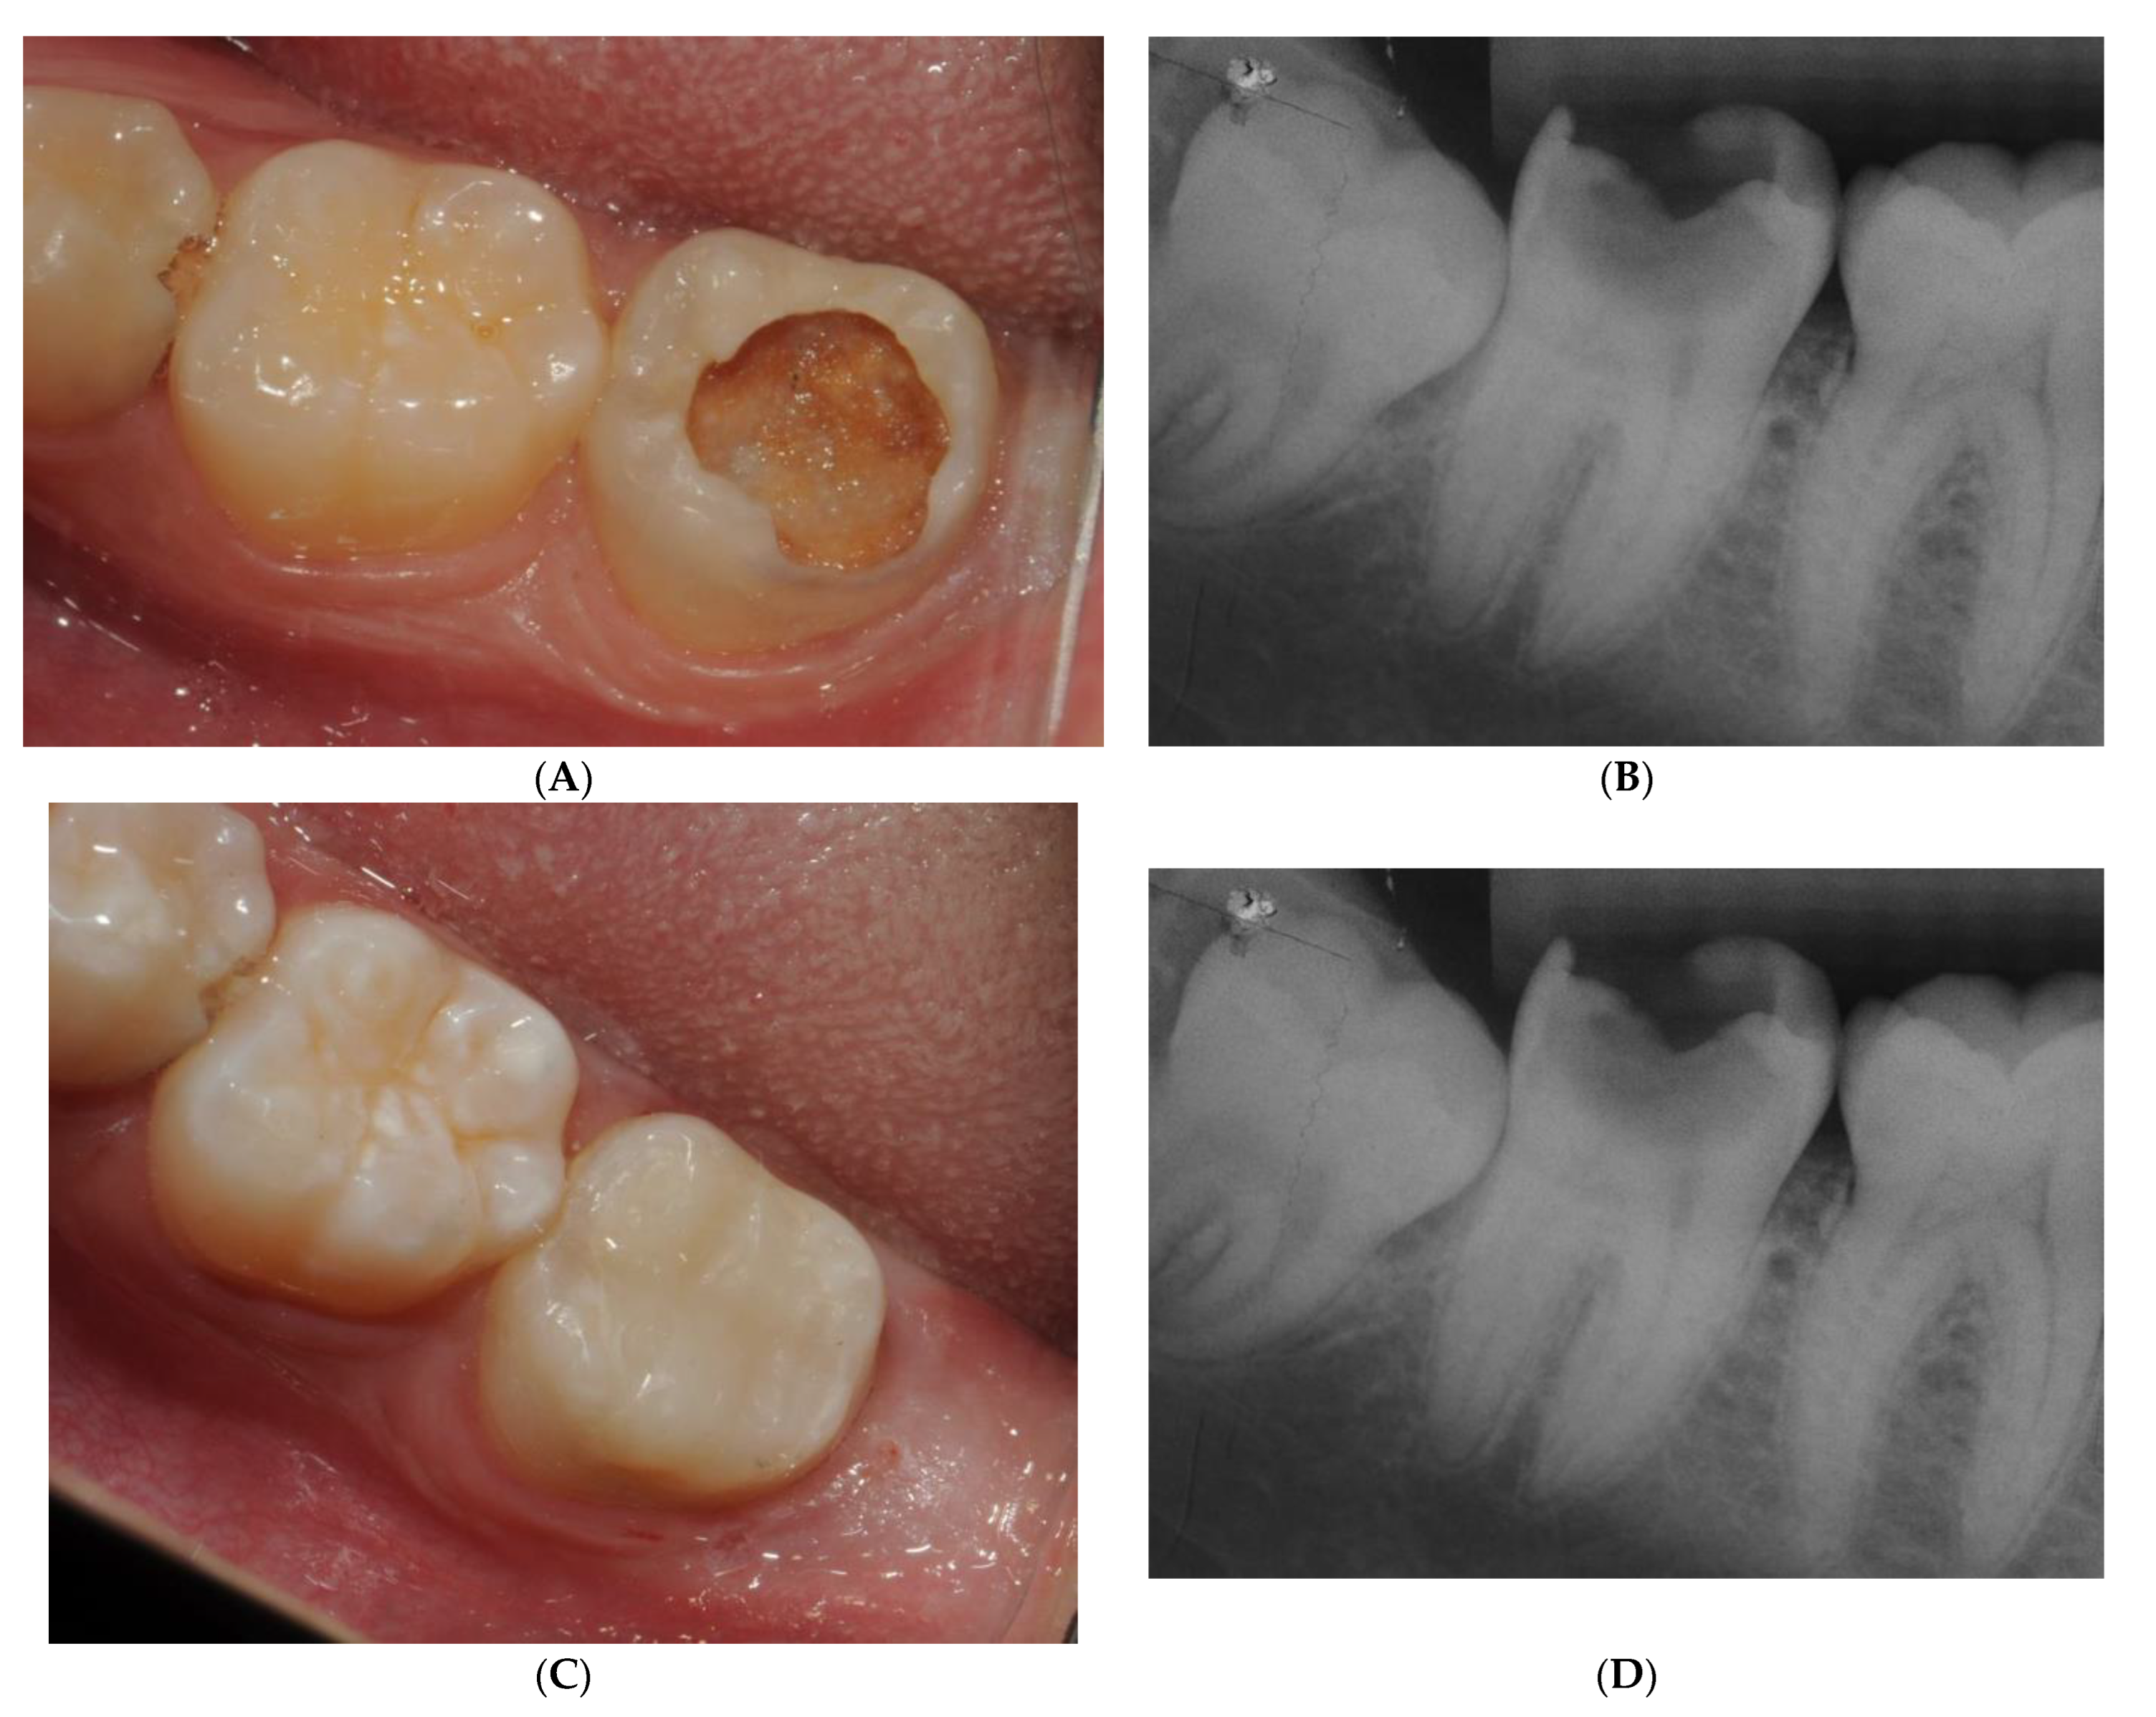

| The clinical case presented was resolved conservatively based, above all, on the patient’s youth and the possibilities of reparative dentin calcification. The cleaning of the caries was carried out using an excavator and chemical methods. Biodentine was used as an indirect pulp protector. The filling was performed with self-etching adhesive with selective etching and bulk fill composite. Does your choice of treatment coincide with the treatment given to the patient? Check more than one option if you consider it | 1. Yes | 31.70 |

| In the clinical image, you can see the resolution of the case, and in the x-ray, you can see the evolution one year after treatment. What do you think? | 1. Conservative methods with the application of bioactive liners are a real treatment option for deep cavities, so I agree with the treatment carried out. | 89.63 |